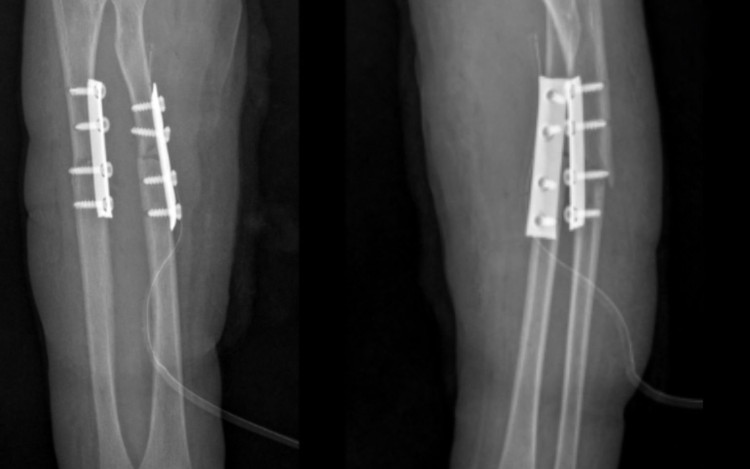

Bệnh nhi N.M.H. (7 tuổi, Bắc Ninh) đến thăm khám tại Bệnh viện Đa khoa Hồng Ngọc trong tình trạng đau nhiều vùng cẳng tay trái, hạn chế vận động sau khi đi xe đạp bị ngã. Kết quả chụp X-quang cho thấy bé bị gãy kín 1/3 trên cả hai xương cẳng tay trái (xương quay và xương trụ), có mảnh xương di lệch.

Gãy kín 1/3 trên hai xương cẳng tay trái gây đau, hạn chế vận động - Ảnh BVCC

Sau khi hội chẩn chuyên khoa, ê-kíp đã thống nhất phương án phẫu thuật kết hợp xương để cố định và phục hồi trục chi. Trước khi tiến hành, bệnh nhi được thực hiện đầy đủ các xét nghiệm tiền phẫu như công thức máu, đông máu, điện tim, X-quang phổi và đánh giá gây mê nhằm đảm bảo an toàn tối đa trong suốt quá trình phẫu thuật.